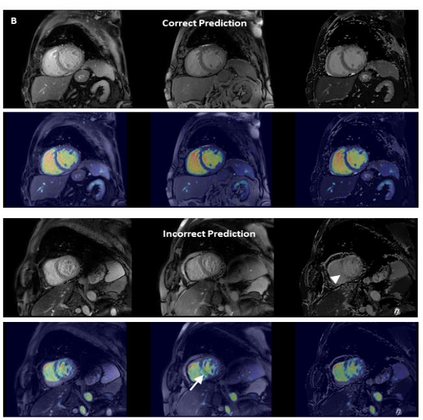

Objectives: To develop an image-based automatic deep learning method to classify cardiac MR images by sequence type and imaging plane for improved clinical post-processing efficiency. Methods: Multi-vendor cardiac MRI studies were retrospectively collected from 4 centres and 3 vendors. A two-head convolutional neural network ('CardiSort') was trained to classify 35 sequences by imaging sequence (n=17) and plane (n=10). Single vendor training (SVT) on single centre images (n=234 patients) and multi-vendor training (MVT) with multicentre images (n = 479 patients, 3 centres) was performed. Model accuracy was compared to manual ground truth labels by an expert radiologist on a hold-out test set for both SVT and MVT. External validation of MVT (MVTexternal) was performed on data from 3 previously unseen magnet systems from 2 vendors (n=80 patients). Results: High sequence and plane accuracies were observed for SVT (85.2% and 93.2% respectively), and MVT (96.5% and 98.1% respectively) on the hold-out test set. MVTexternal yielded sequence accuracy of 92.7% and plane accuracy of 93.0%. There was high accuracy for common sequences and conventional cardiac planes. Poor accuracy was observed for underrepresented classes and sequences where there was greater variability in acquisition parameters across centres, such as perfusion imaging. Conclusions: A deep learning network was developed on multivendor data to classify MRI studies into component sequences and planes, with external validation. With refinement, it has potential to improve workflow by enabling automated sequence selection, an important first step in completely automated post-processing pipelines.